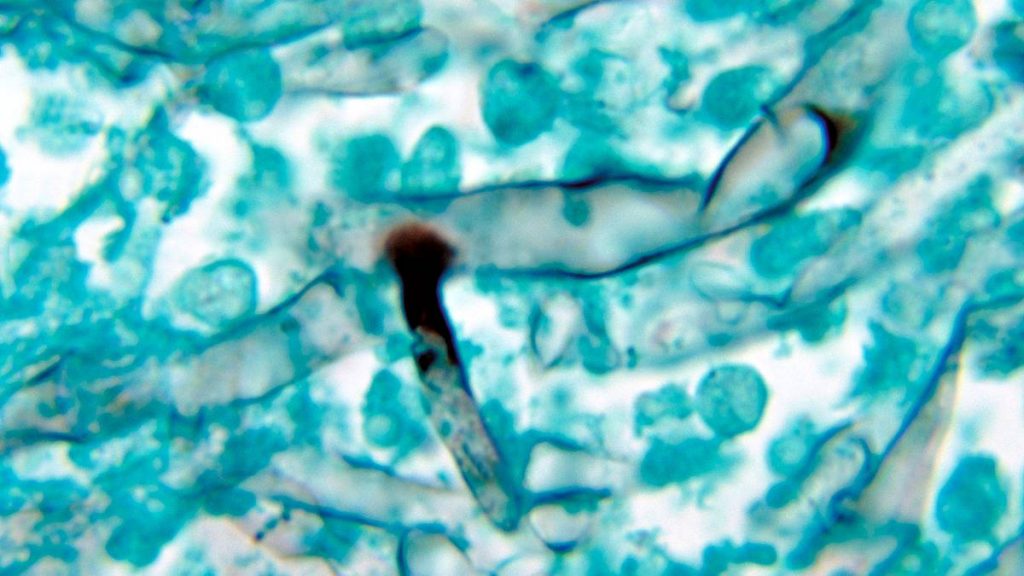

Se trata de la mucormicosis pulmonar, infección poco frecuente pero que agrava la condición de quien la padece. Esta la causan por distintos tipos de mohos del orden mucorales, entre los cuales figura especialmente los Rhizopus u “hongos negros”.

En Chile, hasta ahora, no existen reportes de esta particular enfermedad vinculada a SARS-CoV-2, pero sí de otra con características y pronósticos muy similares: la aspergilosis pulmonar asociada a coronavirus o CAPA, originada también por un hongo (el Aspergillus fumigatus) que en este caso es de color verde, consigna T13.

“En el caso de personas con COVID-19, la infección por 'hongo verde' se diagnostica a través de cultivos o mediante la detección del antígeno (galactomanano) que libera. Mayoritariamente se da en pulmones y en pacientes que llevan varias semanas conectados a ventilación mecánica y bajo tratamiento de corticoides”, acota el director del Cdiei-UV.